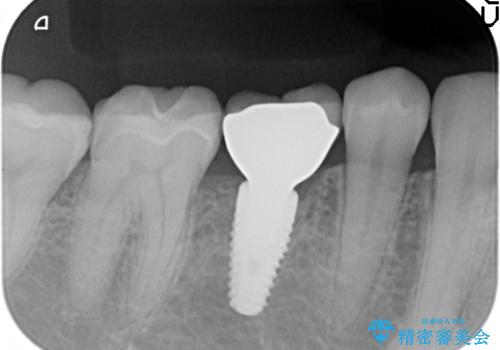

審美的・機能的に良好な位置に埋入するには、骨量が十分ではなかったため骨の造成を併用したインプラント埋入外科手術を行います。

前歯のインプラントを審美的に仕上げるには、インプラント周囲に十分な骨の量と厚みのある歯肉、そして埋入位置の精密な位置付けが重要です。